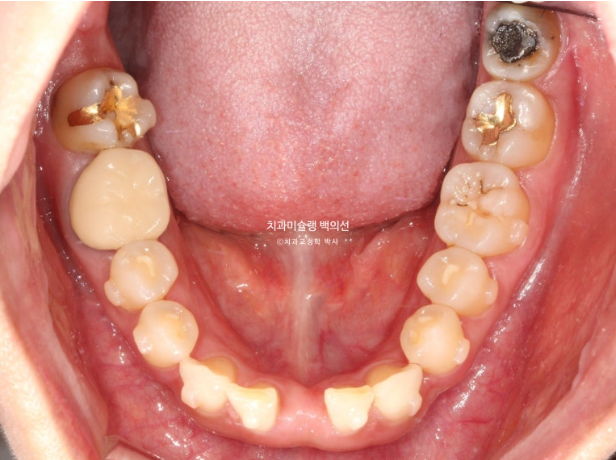

사진에 보이는 구멍은 앞니가 없어 송곳니가 앞니 자리로 이동하고 송곳니와 작은어금니 사이 공간이 벌어져 있습니다.

환자분이 모르고 있던 또 다른 문제는 파란화살표 제 2대구치가 혀쪽으로 쓰러져 있는 것 입니다.

빨간색 치축으로 표시한 치아가 쓰러진 치아입니다.

이 치아는 씹는데 중요한 역할을 하는 치아이므로 반드시 세워주는 것이 좋습니다.

그러려면 쓰러진 큰어금니 바로 뒤 썩은 사랑니는 빼주는 것이 좋습니다

환자분의 안모는 공간을 함부로 모으면 안되는 상황입니다.

즉 입술이 얇고 돌출이 전혀 없는 상황이었습니다.

앞니가 뒤로는 단 1mm도 움직이면 안되는 상황이죠.

따라서 좌우로 분산된 공간을 몰아서 아래 앞니 한 개를 수복할 공간을 마련한 후 임플란트 또는 브릿지로 수복을 하기로 합니다.